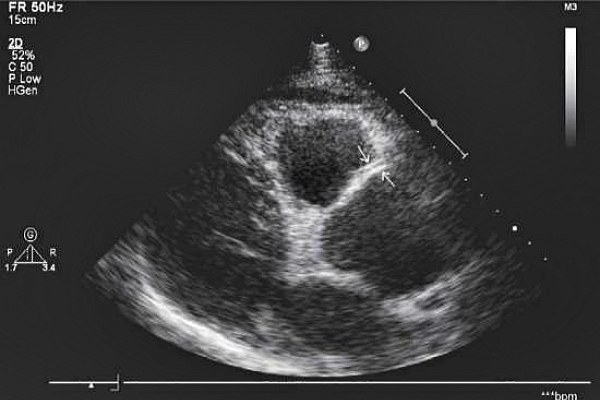

Трансторакальная эхокардиография является наиболее комфортной для пациента. Сердце визуализируется через грудную клетку. Исследование дает быстрые, точные результаты, не требует специальной подготовки. Эти факты делают данную методику предпочтительной для выявления патологий сердца.

Трансторакальная Эхо-Кг

Процедура относится к простым и легко выполнимым как для обследуемого, так и для врача. Никакой предварительной подготовки она не требует. Пациент размещается на кушетке, лежа на левом боку.

На грудную клетку закрепляются датчики небольшого размера, которые подключены к эхокардиографу. Генерируемые ими сигналы проходят к сердцу через межреберные пространства.

Звуковые волны перемещаются в тканях и трансформируются, после чего возвращаются к датчикам.

Эхокардиограф преобразовывает их в электросигналы, а затем производит обработку. В результате на мониторе формируется изображение. Иногда может потребоваться проведение Эхо-КГ с контрастным веществом. Его вводят внутривенно, что позволяет получить цветные изображения различных структур, произвести замеры отверстий в перегородках («овального окна») или определить наличие тромбов в миокарде.